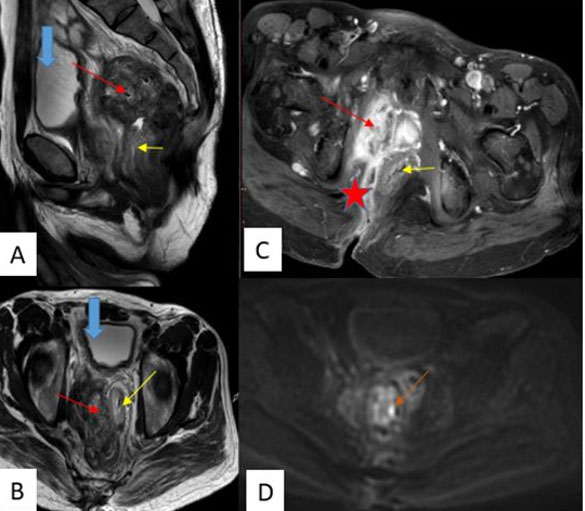

A later magnetic resonance imaging (MRI) was performed showing a retroperitoneal and latero-rectal mass with heterogeneous signal on T2, containing some areas of necrosis enhanced heterogeneously after gadolinium injection with localized restriction on the diffusion sequence. Anteriorly, it exerts a mass effect on the bladder without affecting the upper urinary tract, and laterally, it comes into contact with the obturator muscles and the rectal wall without clear signs of infiltration, with the identification of a fistulous tract between the tumor and the soft tissues of the buttocks (Figure 2).

Figure 2: Abdominal MRI: Sagittal and axial T2 (A, B): retroperitoneal latero-recto-anal multilobulated mass with heterogeneous T2 hypointensity (red arrow), creating a mass effect on the left rectum (yellow arrow) and anal canal, and on the bladder anteriorly (blue arrow), coming into contact with the internal obturator muscle without clear signs of infiltration. T1 after injection of gadolinium (C), and diffusion B1000 (D). This process enhances heterogeneously after gadolinium injection (red arrow), with the identification of a fistulous tract between the tumor and the soft tissues of the buttocks (red star). Localized restriction is also observed on the diffusion sequence (orange arrow).